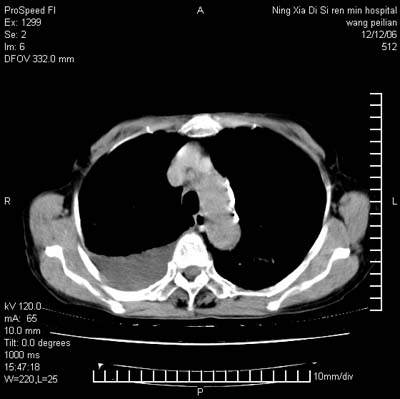

标题: CT5609:胸部:女77 病史不详

两肺可见多个大小不等的结节,左侧有胸水,纵隔淋巴结增大,考虑是细支气管肺泡癌

两肺尖纤维索状影,两下肺结节块状影,且有钙化灶,右胸腔积液。考虑肺结核并胸膜炎。

两肺尖纤维索状影,两下肺结节块状影,且有钙化灶,右胸腔积液。考虑肺结核并胸膜炎肺间质纤维化

考虑:1、慢性支气管炎合并全小叶型肺气肿、间质纤维化;

2、双肺结核;

3、右侧胸膜炎(积液)。

1、双肺继发型肺结核(以纤维、增殖灶为主);

2、右侧胸腔积液;

3、其余符合老年肺改变。

双肺见多个结节状及条索状影,双侧胸腔积液,右侧叶间积液,考虑结核性胸膜炎